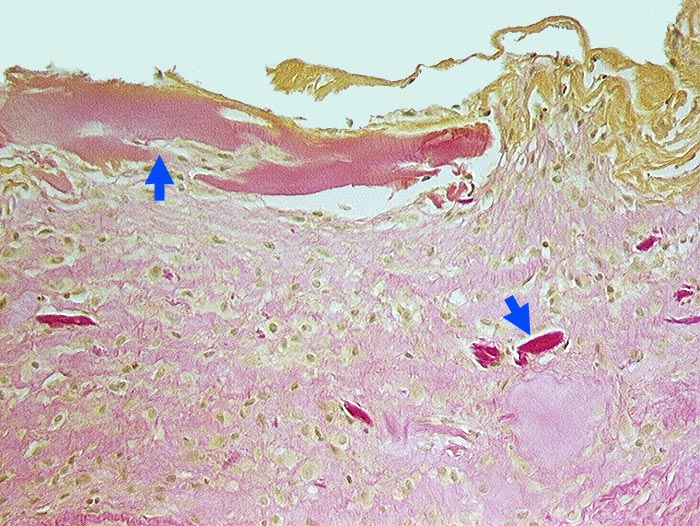

Fibrosierte Synovialis mit gelben Fibrinauflagerungen. Infiltratfreies Stroma mit zahlreichen ► avitalen Knochenfragmenten.

Gonarthrose mit Nekrose der Tibiakondylen.